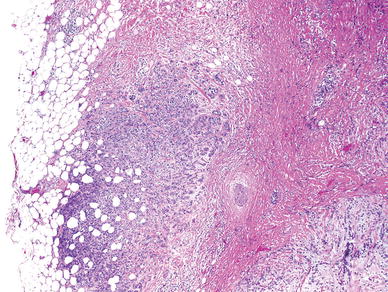

Perhaps the most relevant example of this phenomenon is with carcinoma ex pleomorphic adenoma. Historically and even currently in the clinical literature, [24] carcinoma ex pleomorphic adenoma is automatically considered a high grade malignancy. In most cases, this is true with high grade adenocarcinoma, not otherwise specified (NOS), and salivary duct carcinoma being the most common histologic subtype of the carcinomatous component. However, as many as 15% of tumors are low grade and may behave in a more indolent fashion [5]. More recently, there is evidence to suggest that ‘intracapsular’ carcinoma ex pleomorphic adenoma and minimally invasive carcinoma (<1.5 mm of invasion) ex pleomorphic adenoma (Fig. 1) are also indolent variants that should not be considered equivalent to the typical carcinoma ex pleomorphic adenoma.

Fig. 1

Minimally invasive carcinoma ex pleomorphic adenoma. The pleomorphic adenoma component with sclerosis is seen on the right, and the minor low grade carcinoma component infiltrates the surrounding adipose tissue. This carcinoma was immunophenotypically a myoepithelial carcinoma (stains not shown)